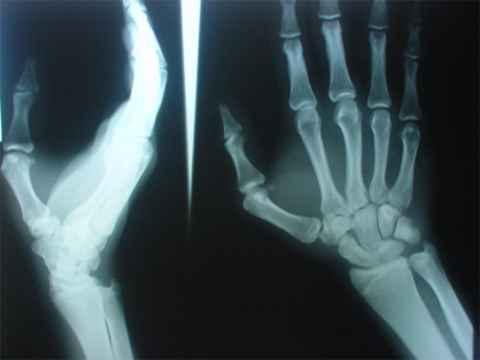

Toreando por el norte de España el novillero El Arqueño, viejo conocido nuestro y amigo de la casa, es cogido volteado y revolteado por el astado con el resultado que vamos a ver.

Manuel arrastra desde hace años una lesión de sintomatología recidivante típica del matador de toros.

La artrosis postraumática de primer dedo de la mano derecha ( en los matadores diestros )

Esta es una lesión irreversible que deforma la articulación y poco a poco, por el continuo hacer diario del profesional cambia y retuerce los huesos de la misma, siendo además muy dolorosa al entrar a matar.

Esta es la lesión que provoca los signos dolorosos cuando vemos los intentos de matar frustrados en las plazas de toros y que quita trofeos como ninguna otra.

Veamos unas imágenes